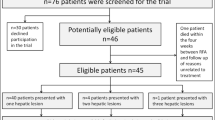

Patient Selection

Informed consent was waived by the Institutional Review Board. All patients who underwent renal cryoablation between May 2014 and July 2017 (duration of the project) and did not opt-out for the use of anonymous data were included. No further exclusion criteria regarding the studied population were used. For validation of the simulation model, data from 19 procedures in 18 consecutive patients treated with percutaneous cryoablation for a renal tumor ≤ 4.5 cm were used. Procedural details are published elsewhere [16]. Demographics are described in Table 1.